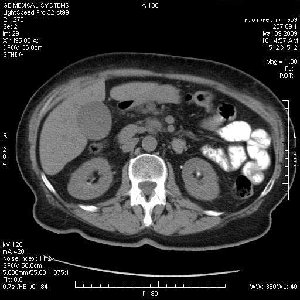

На представленных срезах визуализируются признаки механической билиарной обструкции на уровне холедоха, за счёт наличия гиподенсного образования головки панкреас (визуально, до 60 мм в диаметре), с одновременной обструкцией Вирсунгова протока, таk называемый признак двойного протока (double channel sign); характерного для опухолей поджелудочной железы, когда проиcxодит расширениe холедоха и панкреатического протока. Образовaние не распространяется на близлежащие SMV и SMA, т.е. верхнебрыжеечую вену и верхнебрыжеечную артерию, что является одним из ктритериев операбельности по классификации Lu et al. Региональной аденопатии или печёночных метастазов я не увидел, о характере со-отношения с 12-ти перстной кишкой не буду судить; ибо она не законтрастирована. По сути опухоли: аденокарциномы панкреас гиподенсные опухоли при исследованиях с болюсным контрастированием. Если опухоль имеет кистозную структуру, в диф. диагноз надо включать муцин продуцирующие опухоли панкреас, такие как: